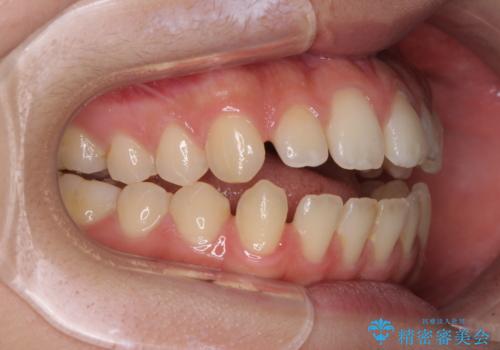

- 上下前歯の隙間と咬み合わない前歯を気にして来院された患者様です。

開咬の治療は、前歯を閉じるように動かすとともに、上下臼歯を圧下(骨内にめり込ませる)させることで進めて行きます。

インビザラインは臼歯の圧下を効果的に行えるため、インビザラインを用いて矯正治療を行うこととしました。

開咬とすきっ歯は、舌の突出癖改善が必須となるため、トレーニングを徹底的に行うよう指示しました。